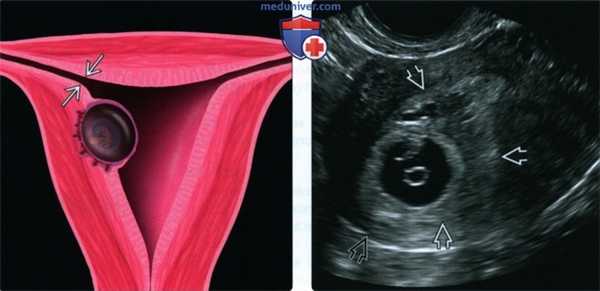

(Слева) На рисунке схематично показана картина при интерстициальной трубной беременности (фронтальное сечение). Плодное яйцо деформирует контур рога матки, в результате чего происходит выбухание и истончение окружающего яйцо миометрия. Соединяющиеся стенки интерстициальной части маточной трубы обусловливают появление признака интерстициальной линии

(Справа) При ТВУЗИ выявляется интерстициальная трубная беременность, окружающий миометрий выглядит нечетким. Виден признак интерстициальной линии соединяющей пустую полость матки с плодным яйцом. (Слева) При 3D УЗИ диагностирована интерстициальная трубная беременность, плодное яйцо явно расположено не в полости эндометрия. Обратите внимание на симптом «клешни» - крайнюю степень истончения миометрия, идущего вдоль границы плодного яйца по дну матки. Разрыв может привести к фатальному кровотечению.

(Справа) На фотографии, сделанной в ходе операции, показан сжатый истонченный миометрий на стороне интерстициальной трубной беременности. Плодное яйцо было удалено (врезка), и в нем четко виден эмбрион и прилежащий к нему желточный мешок.